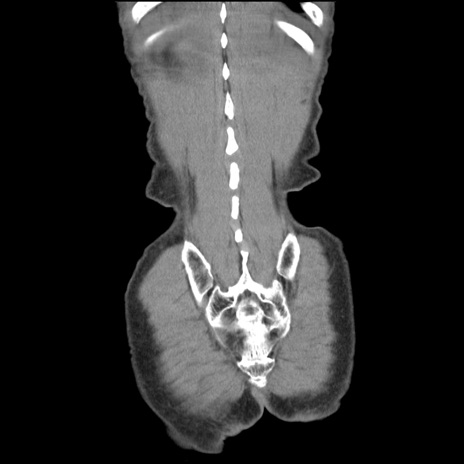

症例11(冠状断像)

【症例】 60歳代男性

【主訴】 下腹部痛

【現病歴】 本日夜中より下腹部痛の症状認め、受診。

【既往歴】 膀胱癌(膀胱全摘+尿管皮膚瘻術) 、胃癌術後

【身体所見】 BT 35.3℃、PR 58/min、BP 136/98mHg、腹部平坦、軟、腸蠕動音±、ストマ留置あり、左上腹部~正中部に圧痛あり、反跳痛なし。

【データ】WBC 5100、CRP0.01